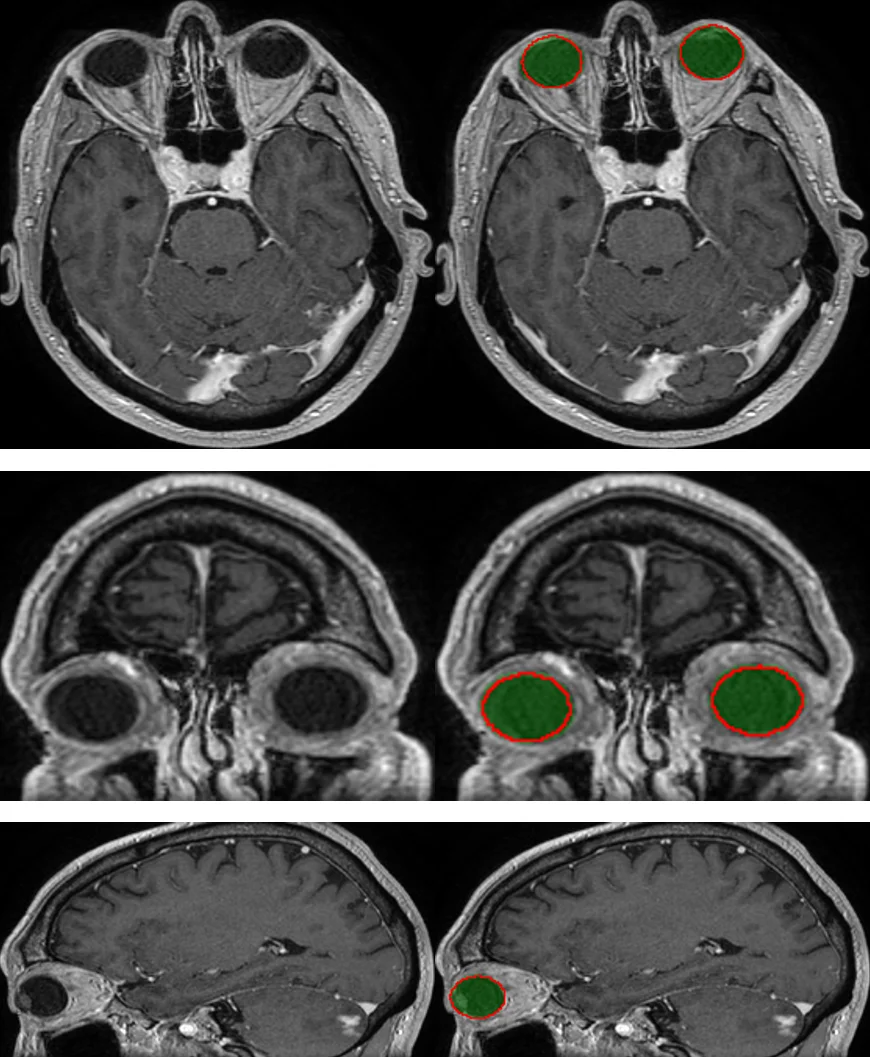

본 논문은 8가지 뇌 위험 장기(눈, 수정체, 시신경, 시교차, 뇌하수체, 해마, 뇌줄기, 뇌)를 MRI에서 자동으로 분할하는 2D U‑Net 기반 모델을 제안한다. 비배타적 클래스와 일부 장기에 대한 라벨 누락 문제를 해결하기 위한 가중치 기반 손실 함수와 샘플링 전략을 도입하고, 시신경‑눈‑시교차 연결성을 그래프 최단경로 알고리즘으로 후처리하여 해부학적 일관성을 확보한다. 44개의 학습용 MRI와 50개의 독립 테스트 MRI에서 평균 거리 오차 0.1~0.7 mm, 96 %의 임상 허용도를 달성하였다.

후처리 단계에서는 해부학적 일관성을 강화하기 위해 그래프 기반 최단경로 알고리즘을 적용한다. 시신경은 눈과 시교차 사이를 연결하는 연속적인 구조여야 하므로, 신경망 출력 확률을 그래프의 엣지 가중치로 변환하고, Dijkstra 알고리즘으로 최소 비용 경로를 찾아 시신경을 재구성한다. 이 과정은 시신경이 끊어지거나 비현실적인 형태로 분할되는 오류를 크게 감소시킨다.